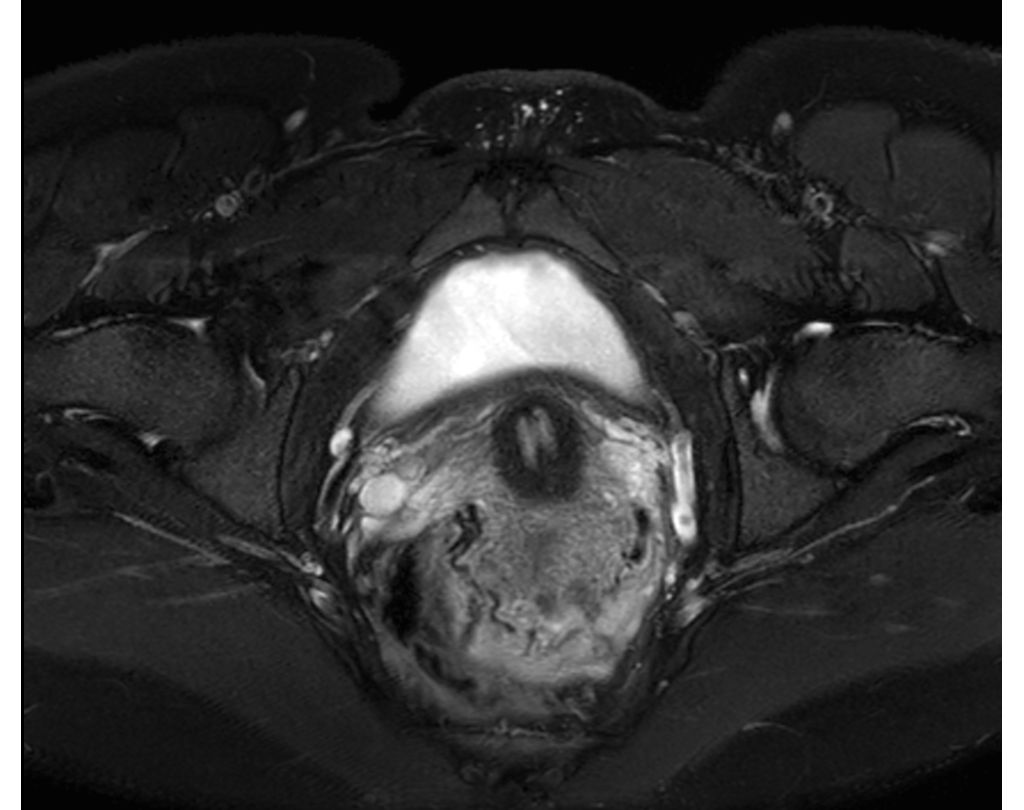

mDIXON XD TSE brings a new dimension to fat suppression by providing uniform, complete and consistent fat-free imaging and up to four image types in one single scan, including with/without fat suppression contrasts, in routine scan times and resolution simultaneously. mDIXON XD TSE will enable you to enhance your imaging strategies by simplifying your routine TSE procedures.